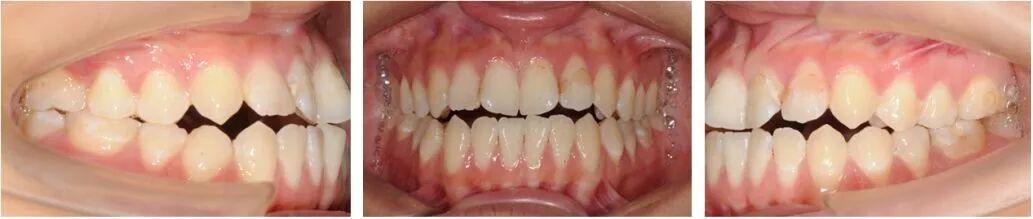

口腔检查:

上下牙弓呈方圆形;双侧尖牙、磨牙III类关系;21牙与31牙呈切合;前牙呈现约1 mm的局部开合;下颌中线较上颌中线左偏1 mm。

模型分析:

上颌拥挤度:1.5 mm,下颌拥挤度:1.5 mm。Bolton指数:全牙比为86.70%,前牙比为75.5%。患者上下颌牙列均存在前牙段轻度的拥挤,前牙和全牙的bolton指数均偏小,提示上颌牙齿牙冠宽度偏大。